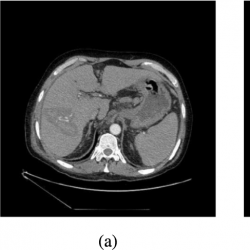

Some matching examples imply that the result could be improved even more. For example, the models of the source (Fig.

4a) and target (Fig.

4b) slices, where the breastbone is not visible, are expressed in red and blue in Fig.

4c, respectively. The difference between models is in the top middle part of a model, where there is no bone tissue. These models are very similar, where the bone tissue is present. Therefore, a disadvantage of the total least-squares strategy is that it considers, with the same importance, the places of the model, where there is no bone tissue in the slice.

Fig. 4

Source (a) and target (b) slices of the same position, respectively; models of these slices (c).